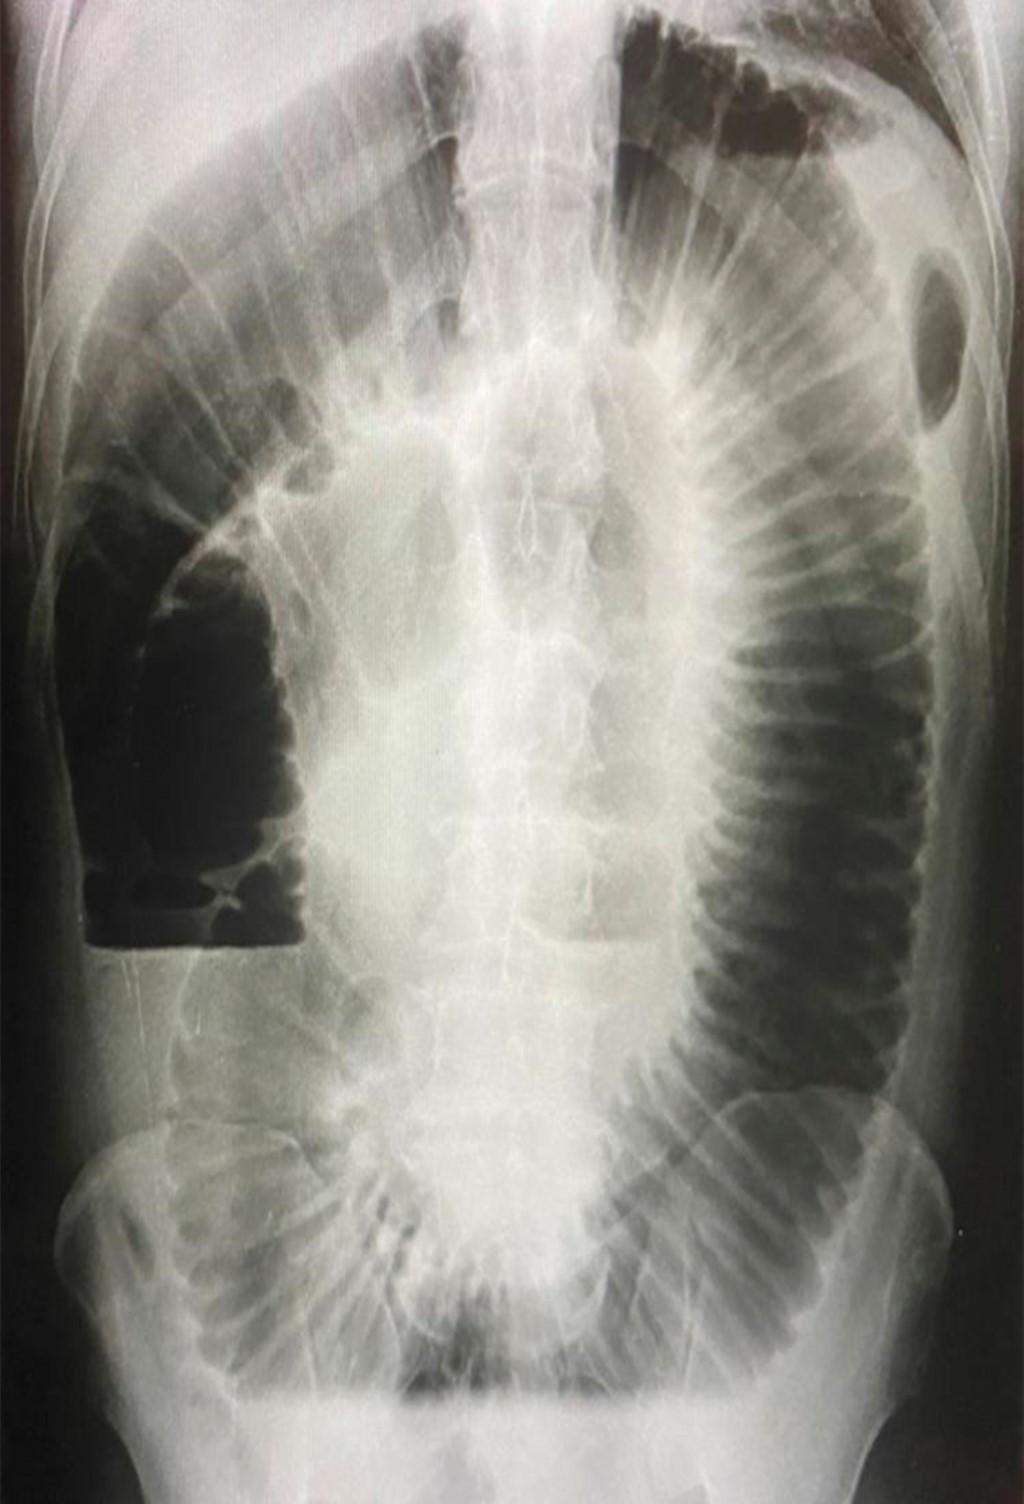

Debido a la pobre respuesta al manejo médico conservador durante 24 horas, con colocación de sonda nasogástrica y ante la imposibilidad de contar con un estudio complementario como una tomografía axial computarizada de abdomen, se decide pasar a quirófano para realizar laparotomía exploradora, con un diagnóstico preoperatorio de oclusión intestinal alta; con hallazgos de oclusión intestinal por compresión duodenal extrínseca y rotación intestinal incompleta, duodeno situado a la derecha de la línea media, bandas peritoneales de Ladd (Figura 3), dilatación importante duodenal (Figura 4), con fijación incompleta del ángulo hepático del colon en posición anormal, presencia de estenosis parciales de yeyuno a 15, 25 y 35 cm del duodeno, se aprecian dos venas varicosas de 1.5 cm de diámetro, que recorren el borde mesentérico del yeyuno en aproximadamente 150 cm (Figura 5), yeyuno con atrofia en sus primeros 100 cm y ángulo hepático del colon localizado a la derecha de la línea media.

Figura 3